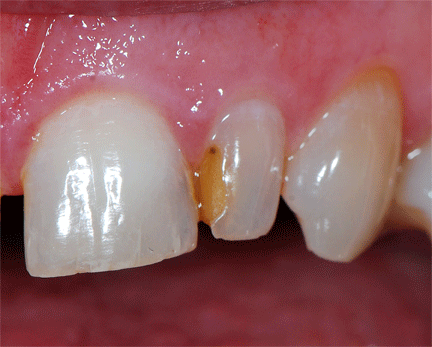

After full contour was achieved, the Epitex clear strip was removed. Tightness of the contact was verified with floss to ensure that the new restoration was making intimate contact with the adjacent tooth. Epitex finishing strips (fine and extra-fine) were used interproximally to achieve a smooth well-contoured surface. The anatomy was refined with safe-ended, 12-bladed finishing carbide burs (Ultimate F&P Kit, GC America Inc.) in a high-speed handpiece with water (figure 5). Occlusion was checked with articulating film (Accufilm II, Parkell Inc.) and adjusted with the Ultimate F&P Kit.

Figure 5: Finishing carbides were used for the final contouring of the restoration. Then, the restoration was polished with a polishing cup, and Epitex strips in medium and extra-fine grit were used interproximally.

Following anatomy refinement, final polishing was achieved using one-step, diamond-impregnatedabrasives from the Ultimate F&P Kit in a slow-speed handpiece to achieve a high gloss. These one-step polishers are available in point, cup, and wheel (knife-edge) shapes to accommodate polishing different tooth surfaces. The author recommends using an electric slow-speed handpiece (if one is available) with water because it helps to remove debris on the surface from the abrasive point, and it seems to yield a better gloss than an air-driven slow-speed handpiece. The final result is a natural-looking direct restoration that blends well with the adjacent tooth and has a high-gloss finish (figure 6).

Figure 6: The final restoration following finishing and polishing. Gingiva that has been irritated by the interproximal finishing strips will heal uneventfully.